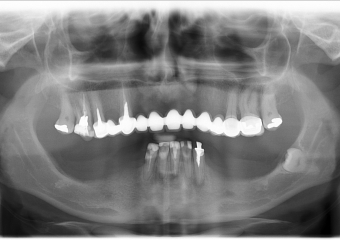

Raio -x inicial em 2014 - Clínica Cliniface

Raio -x inicial em 2014